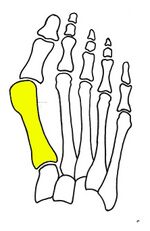

Syndesmosis procedure addresses specifically the two fundamental problems of metatarsus primus varus deformity that gives rise to the bunion deformity. They are leaning and instability of the first metatarsal bone . Syndesmosis procedure uprights the leaning first metatarsal bone with strong binding sutures between it and the second metatarsal bone (Fig. 2) and then also stabilizes it uniquely by creating a fibrous connecting bridge between these two bones (Fig. 3, 4). First metatarsal bone can be readily realigned because by definition of the metatarsus primus varus deformity its first metatarsal is abnormally loose and mobile.[citation needed]